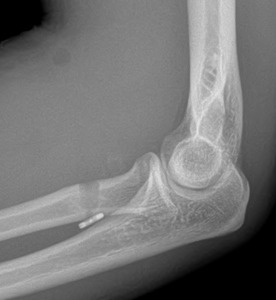

Concerning physical exam, he presented with weakness for elbow flexion and forearm supination. The stump was not palpated in the antecubital fossa but proximal to the elbow crease, and the “reverse Popeye’s sign” was present (Alentorn-Geli, Assenmacher, and Sánchez-Sotelo 2017). And MRI was ordered (Figure 1), and the patient was scheduled for surgical treatment.